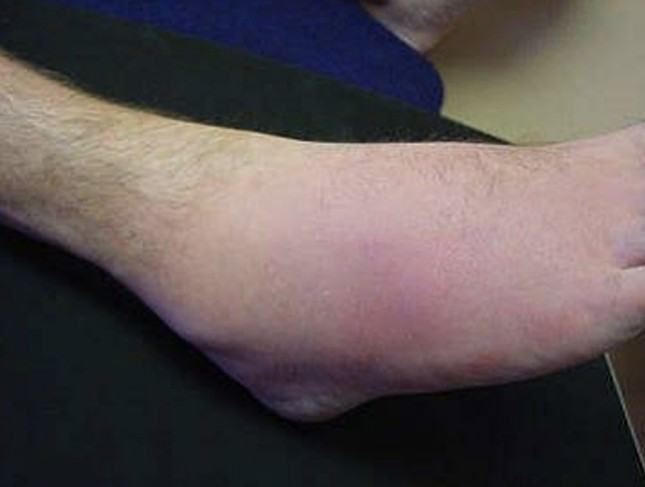

Hot swollen ankle

A 55-year-old man presents with acute atraumatic ankle pain and a low-grade fever.

2024 Term 1 Wk 4 Archived